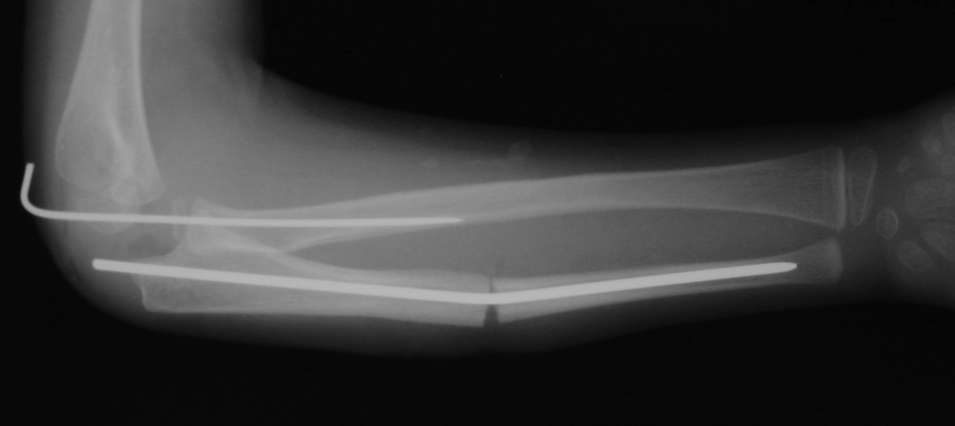

Иллюстрация к лечению застарелого повреждения Монтеджиа

Пациентка клиники детской травматологии ЦИТО

Многоуважаемые коллеги, всем большое спасибо!!! Да, здесь было повреждение Монтеджиа, когда нарисовал скиаграмму все стало понятно. Мне очень понравились рекомендации Константина Требухина, только немножко видоизменил; я считал так, если деформацию исправить то локт/кость должна удлиниться, и во вторых, если на аппарате низвести лучевую кость, то может наступить позиционное несоответствие в дистальном радиоульнарном сочленении. 28.02.08г операция - шарнирная остеотомия локтевой кости на уровне деформации, далее вскрыт плечелучевой сустав, удалены рубцовые тканы, после исправления варусной деформации и создания физиологического изгиба локтевой кости головка луча легко вправился, из части рубцовой ткани сделана пластика кольцевндной связки, трансартикулярная фиксация спицей, локтевая кость двумя спицами.

оперировали подобный случай около 6 мес назад. Отличие только в одном- давность травмы была до 2х лет. Использовали методику описанную в "Pediatric fractures and dislocations" Lutz von Laer, M.D.

Артротомия, иссечение рубцов, остатков кольцевидной связки. На проксимальный отдел локтевой кости стержневой аппарат (рекомендуют

Compact II выпущеный Stryker Howmedica, но за неименеем...), остеотомия проксимального отдела локтевой кости, вправление головки лучевой кости, замыкание аппарата, проверка стабильности головки

лучевой кости в движении, ушивание без пластики кольцевидной связки.